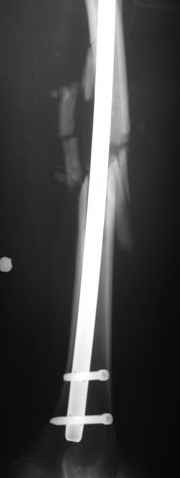

В нашем случае 21 летний боец уличного фронта, фиксацию провели на следующий день, зафиксирован интрамедуллярным штифтом. Не стали делать первичную хирургическую обработку точечной раны, зафиксирован как есть. Клинические снимки:

Конечно, наш случай не эталон, возможно, на месте вам виднее, может быть, нет необходимости ориентироваться на зарубежные ссылки, если получается лечить аппаратом Илизарова на месте, почему нет? Необходимо посмотреть собственный арсенал, чем фиксировать, и какая теория, иначе любой отличный метод можно превратить в источник остеомиелита.